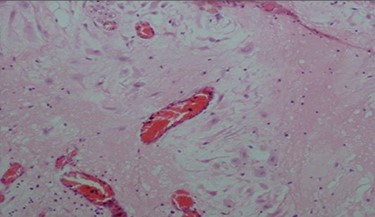

The pathologic examination showed an appendix of 6 × 1.5 cm with a constricted lumen suggesting appendiceal obstruction (Fig. 1). Microscopic examination showed subserosal deciduosis with large polygonal decidual cells, eosinophilic abundant cytoplasm and round nuclei with prominent nucleoli. A hyperplasic lymphoid reaction was found in the submucosa and mucosa (Figs 2 and 3).

Large decidual cell with abundant eosinophilic cytoplasm and round nuclei with prominent nucleoli.

Regarding the differential diagnosis with malignant tumors, a morphological examination of the removed tissues is the ‘gold standard’. Deciduosis is characterized by nodular architecture, composed of large cells with well-defined borders and eosinophilic cytoplasm [7]. Decidual cells are typically perivascular. They appear as large cells with an eosinophilic cytoplasm, and round nuclei with prominent nucleoli. Mitotic activity and/or nuclear atypia are absent. Immunohistochemistry staining is used when deciduosis presents pseudo-tumoral or infiltrative characteristics in order to exclude a peritoneal mesothelioma or a primary or metastatic peritoneal cancer [9].